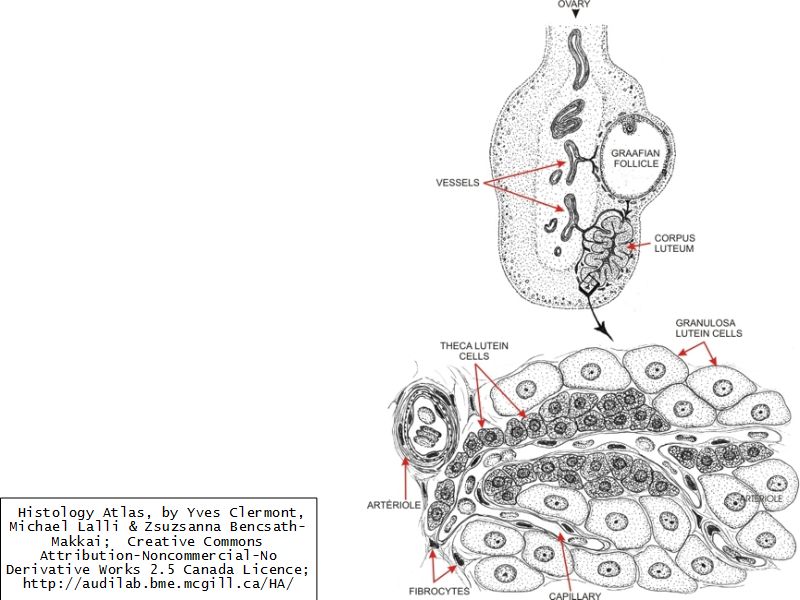

Corpus luteum

Slide 91

Corpus luteum

- Two major cell types

- Granulosa lutein cells

- modified granulosa cells

- Theca lutein cells

- modified theca interna cells

- Many capillaries

Granulosa lutein cells

- Modified granulosa cells

- Large - 30µm

- Pale cells

Theca lutein cells

- Modified theca interna cells

- Smaller - 15µm

- Dark stained